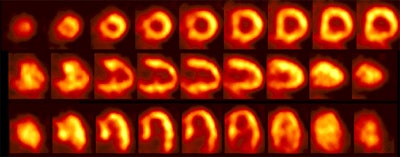

|

Rb-82 rest perfusion examination |